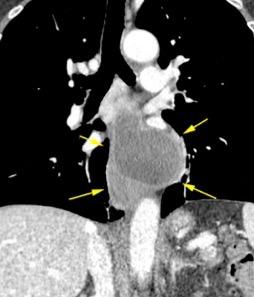

Ganglios retroperitoneales (flechas negras)

germinales del testículo izquierdo Nódulos pulmonares múltiples. (flechas verdes). Ganglios paratraqueales. (flechas amarillas). Dudoso ensanchamiento retrocrural (flechas negras)

Panda A et al. “Straddling Across Boundaries”. Thoracoabdominal Lesions: Spectrum and Pattern Approach. Curr Probl Diagn Radiol, 2015